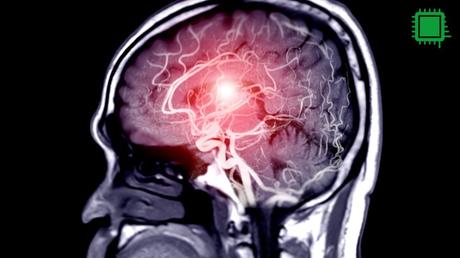

La neuropredicción es una técnica basada en el uso de neurociencia para intentar predecir el comportamiento violento. Para ello, los científicos utilizan tecnologías como la resonancia magnética funcional (fMRI) para observar la actividad cerebral y correlacionarla con el riesgo de que una persona cometa un delito en el futuro. Por ejemplo, algunas investigaciones han encontrado que la baja activación de áreas cerebrales como la corteza cingulada anterior (CCA) se asocia con un mayor riesgo de violencia. Este tipo de estudios ha llevado a algunos defensores de la neuropredicción a argumentar que, si el sistema de justicia pudiera identificar a las personas con mayor riesgo de reincidencia, sería posible intervenir para evitar futuros delitos.

Las técnicas de neuroimagen, como la fMRI, pueden ofrecer información valiosa que complemente las pruebas psicológicas tradicionales. Por ejemplo, estas técnicas podrían ayudar a identificar áreas del cerebro relacionadas con la impulsividad, lo que permitiría desarrollar programas de intervención específicos para cada recluso. Este enfoque respetaría la capacidad de las personas para cambiar su propio destino, trabajando de manera proactiva para su eventual reintegración social.